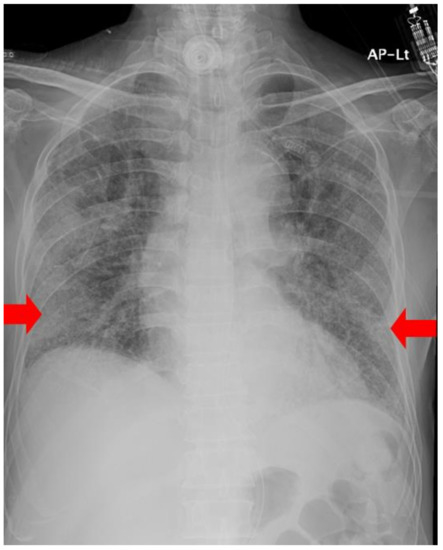

| Chest radiography | GGO in BLLF | Increased GGO | Increased GGO | Decreased GGO | Decreased GGO | Decreased GGO | No interval change | No interval change |